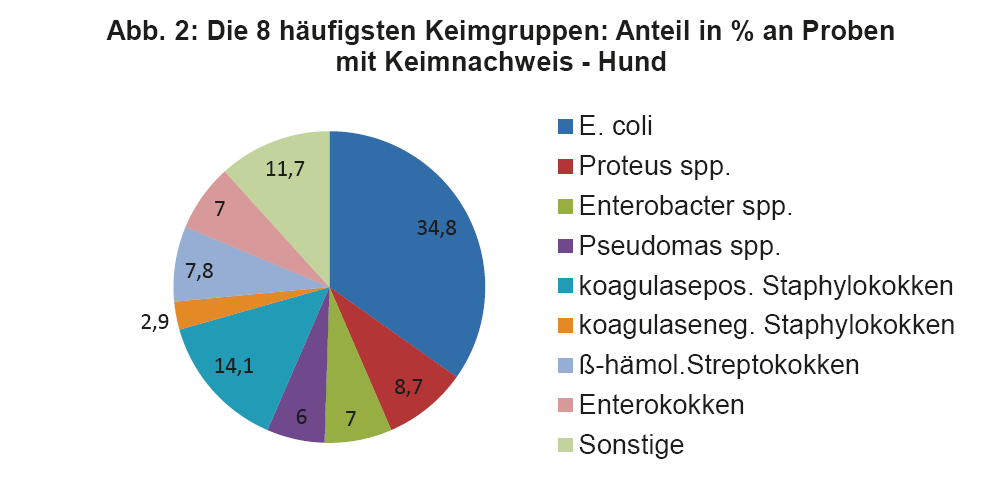

- Abb. 2: Die 8 häufigsten Keimgruppen: Anteil in % an Proben mit Keimnachweis – Hund

Wie bereits erwähnt, müssen die Therapieempfehlungen aus den ISCAID Richtlinien an unsere lokalen Verhältnisse angepasst werden. Daher ist es wichtig, sich regelmäßig über die aktuellen Keimnachweisraten und Resistenzmuster bei HWI zu informieren. Dies sollte allgemein, aber auch bezogen auf die eigene Praxis/Klinik, erfolgen. Regelmäßig durchgeführte BU bei HWI versorgen den Praktiker mit den wichtigen Zahlen. Man soll z.B. für die Ersttherapie keinen Wirkstoff auswählen, gegen welchen mehr als 10% der eigenen Patienten Resistenzen aufweisen. Da immer noch häufig Spontanurinproben statt Zystozenteseharn für die BU eingesandt wird, ist es wichtig, dass eine quantitative Auswertung der BU erfolgt, um Kontamination von Infektion abzugrenzen. Das Labor sollte die Antibiogramme nach den Standards von CLSI/EUCAST durchführen, wie es bei LABOKLIN der Fall ist (s. LABOKLIN aktuell 1/2015). In Abb. 2 und 3 sehen Sie die häufigsten Keimnachweise bei Hund und Katze aus dem Jahr 2013.

Die vier wichtigsten Keime beim Hund sind E. coli, Staphylokokken, Proteus spp. und ß-hämolysierende Streptokokken. Diese machen zusammen über 65% der Nachweise aus.